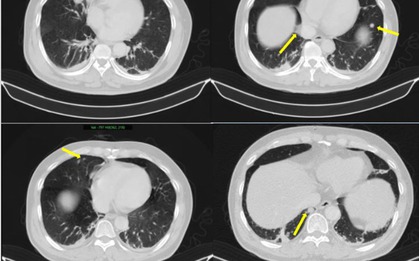

Nuốt nghẹn, sụt 5 kg, đi khám phát hiện mắc hai loại ung thư

Sức khỏe

-

Người đàn ông nhập viện vì nuốt nghẹn, sụt 5 kg trong một tháng, đi khám phát hiện cùng lúc hai ung thư biểu mô vảy ở thực quản và hầu miệng.